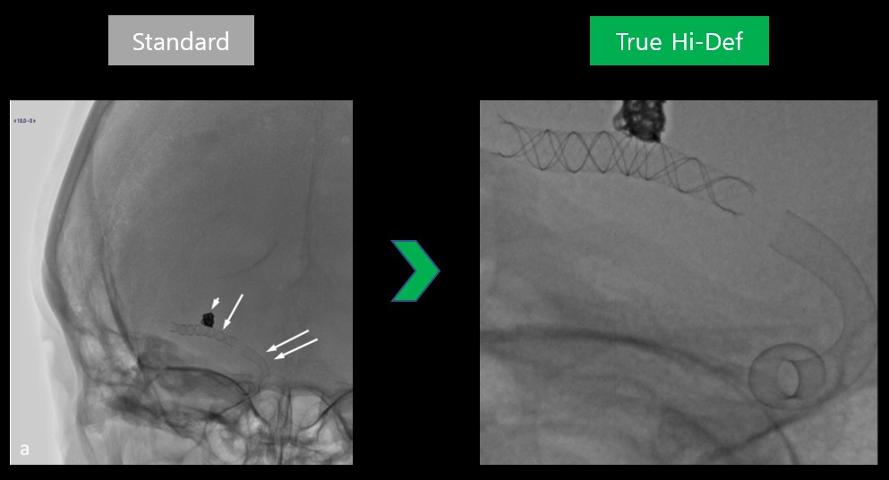

알피닉스 True Hi-Def Edition(우측)은 초고해상도 영상을 통해 중재시술을 위한 최적의 환경을 제공한다. 사진=캐논메디칼

캐논이 세계 최초로 개발한 True Hi-Def 디텍터는 기존 디텍터의 픽셀사이즈(150~200um)를 76um까지 대폭 줄여 영상의 해상도를 2.5~3.2lp/mm에서 최대 6.6lp/mm으로 2배 이상 향상시켰다.

회사측은 "1.5인치까지 확대시킨 영상을 제공해 시술 정확성을 획기적으로 높일 수 있도록 했다. 최대 6인치 수준까지만 확대가 가능한 기존 디텍터들 대비 4배 이상의 성능을 가지고 있다. 이를 통해 의사들은 시술시 기구들이 실제로 혈관내에서 어떻게 설치됐는지 정확하게 확인할 수 있다"고 설명했다.